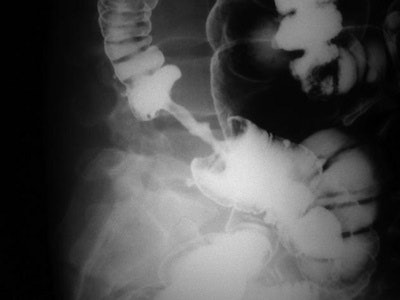

On CT, the vertebral facet joint space can look like a hamburger. All images courtesy of Fathima Hasan Mohamed.

Hamburger: "My own personal favorite," Mohamed commented. On axial CT, the vertebral facet (apophyseal) joint space can look like a hamburger. When the facet joint is dislocated, the articular facets become uncovered, or naked, and this is also called naked facet sign. This CT sign is characteristic of a flexion-distraction injury and indicates severe ligamentous disruption and spinal instability. It may be unilateral or bilateral, depending on the facet dislocation.